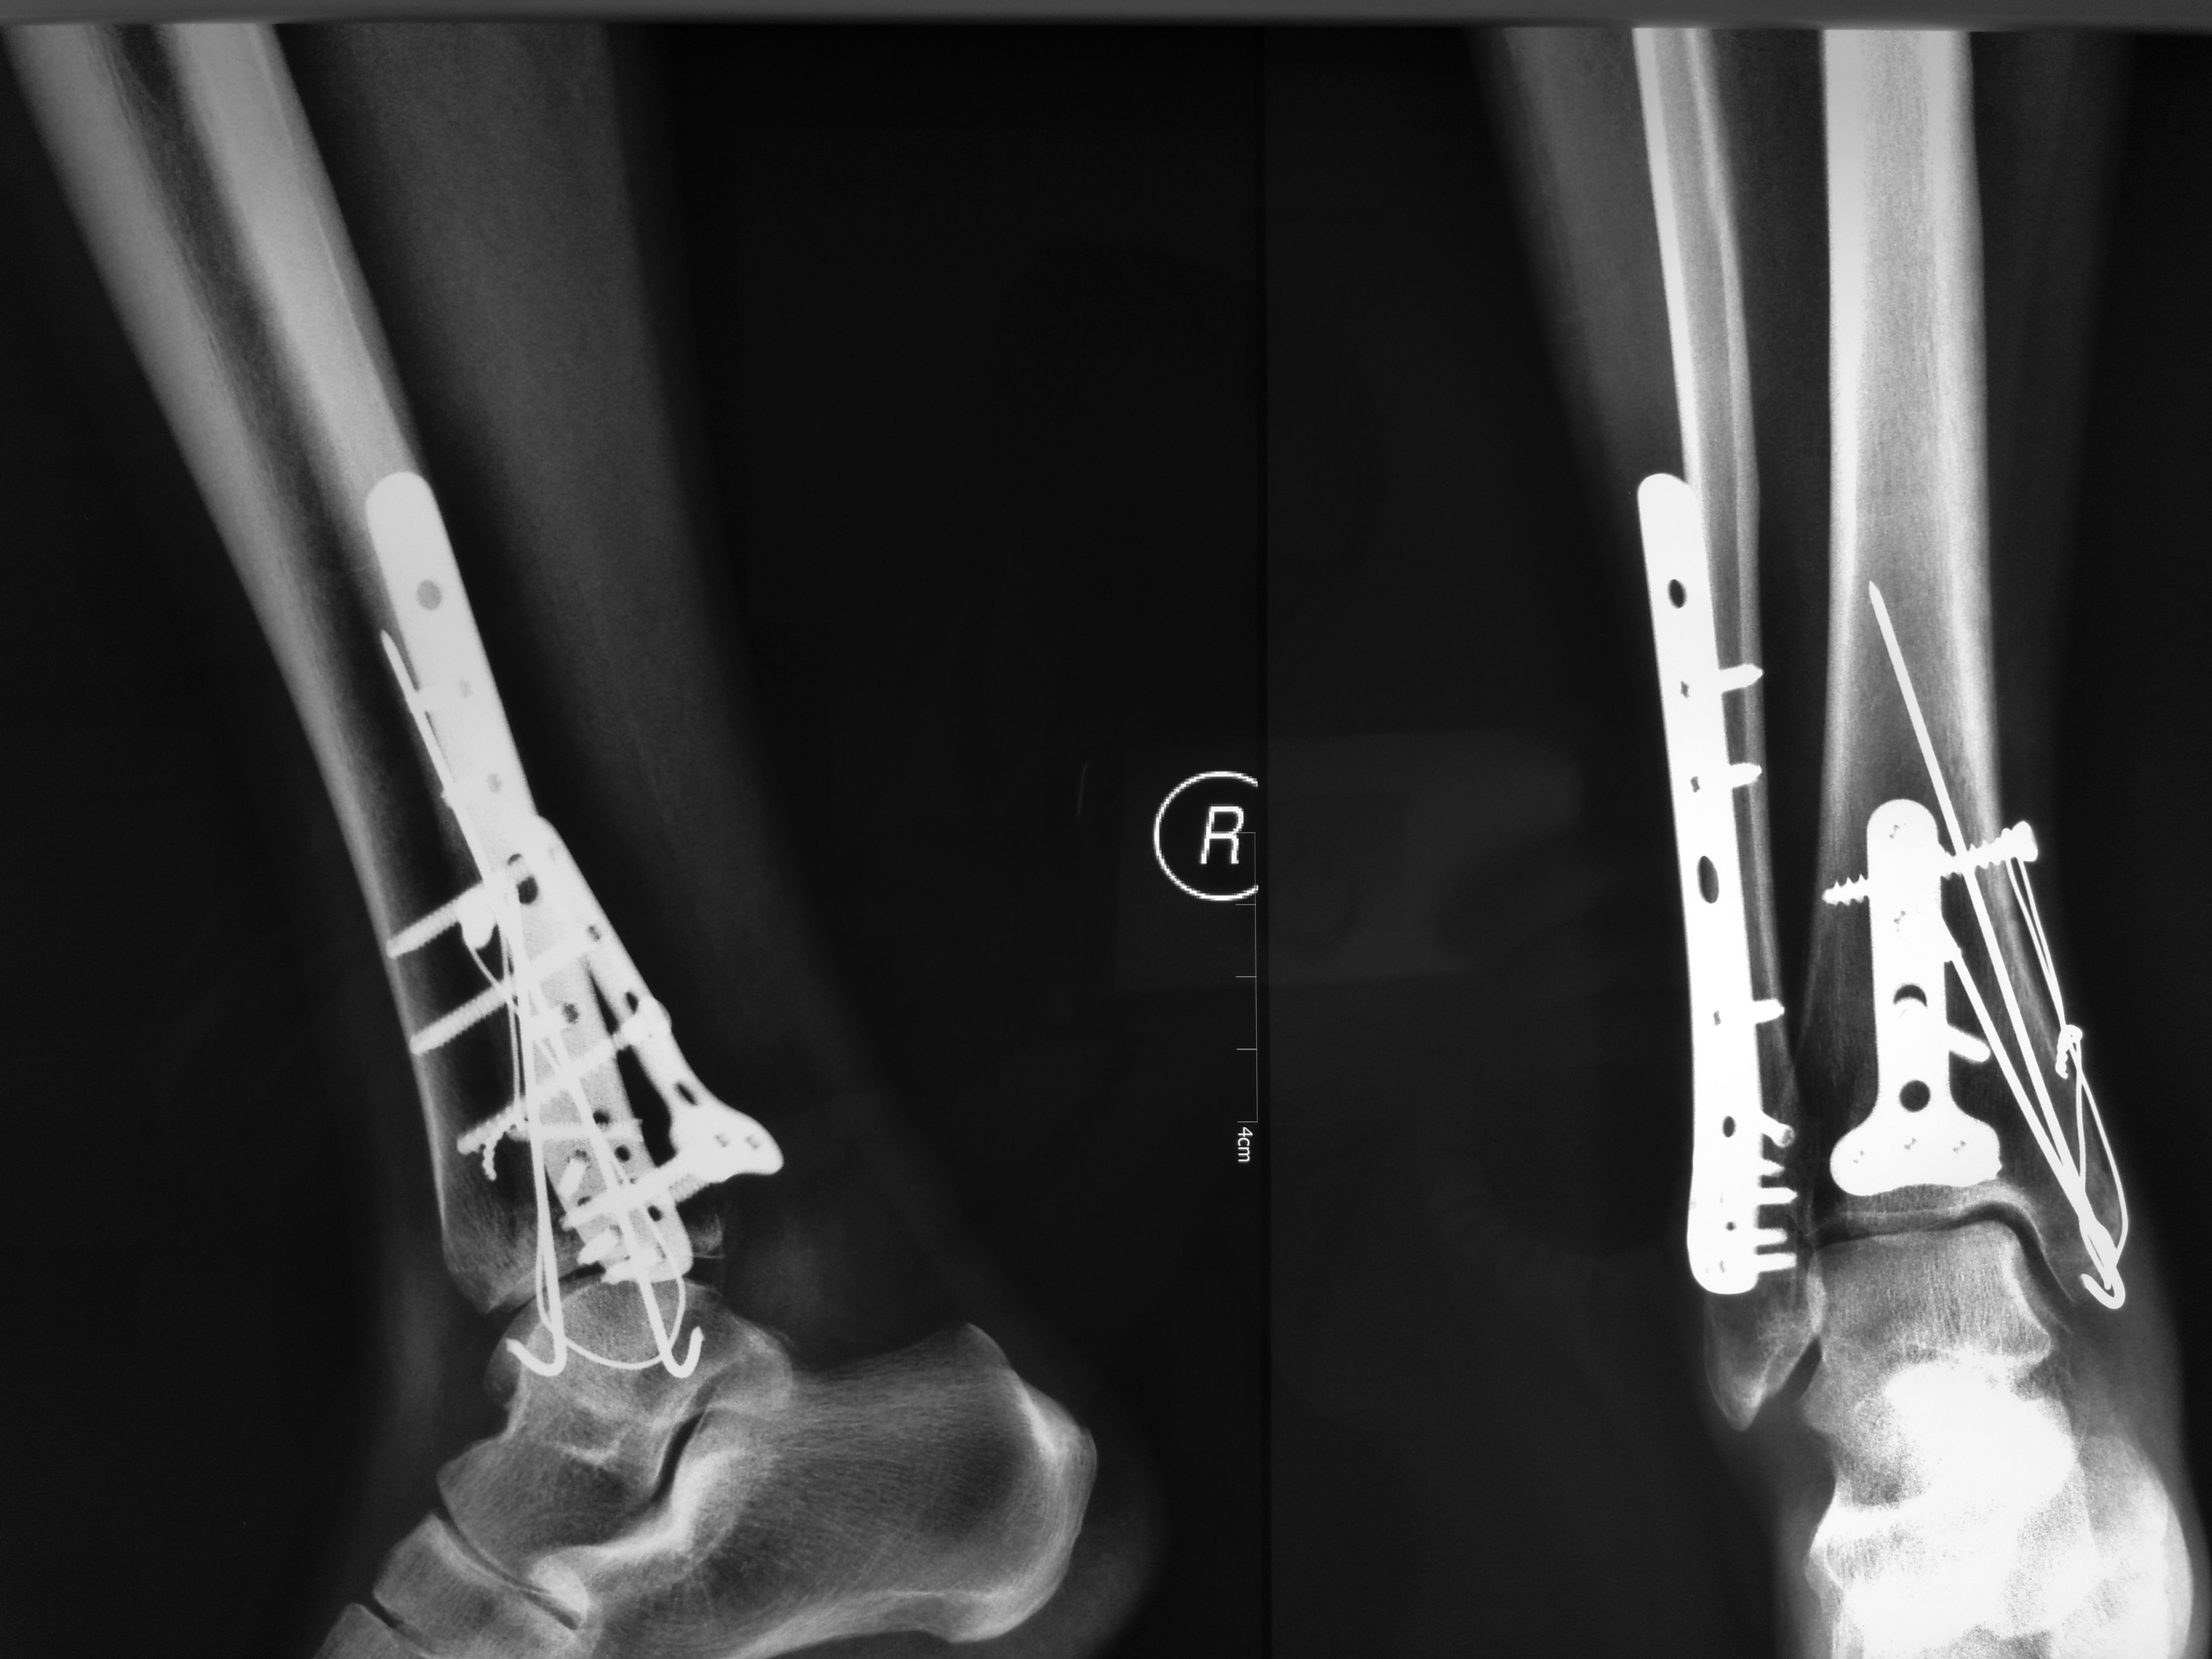

三踝骨折 - 好大夫在线

三踝骨折一例讨论分型及治疗